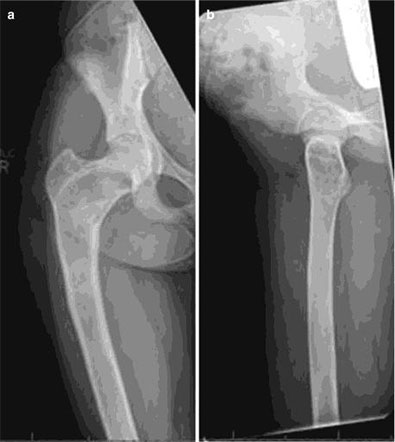

Bone tumors are rare lesions. A large part of these tumors are benign lesions, and they often occur by chance during radiological examinations for another reason. As a complaint, they usually show swelling and pain. Rarely, it is diagnosed after causing a fracture in the place where it was. Osteoid osteoma, osteochondroma (exostosis), enchondroma, non-ossifying fibroma, eosinophilic granuloma, simple bone cyst, fibrous dysplasia and intraosseous lipoma/ganglion are the most common lesions of benign tumors.